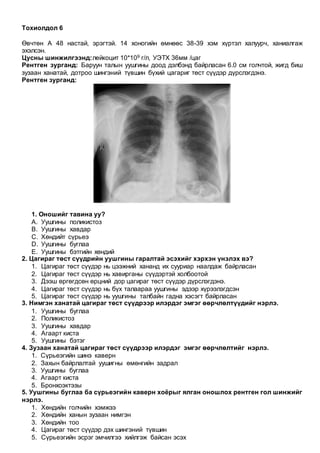

Өвчтөн. Д. 57 настай, эрэгтэй. Нуруугаар үе үе өвдөнө, өвдөлт гуяны ар талаар дамжина

гэсэн зовиуртай мэдрэлийн эмчид хандав.

Бодит үзлэгт: нуруу бөхийж, нурууны булчин чангарсан, Ласегийн шинж эерэг.

Бүсэлхийн нурууны соронзон резонанст томографийн зураг:

1. Онош тавина уу?

1. Бүсэлхийн нурууны L4/5 дискний ивэрхий

2. Бүсэлхийн нурууны L4/5-ын спондилез

3. Бүсэлхийн нурууны L4/5-ын остеохондроз

4. Бүсэлхийн нурууны L4/5, L5/S1 дискний ивэрхий

5. Бүсэлхийн нурууны L4/5-ын спондилит